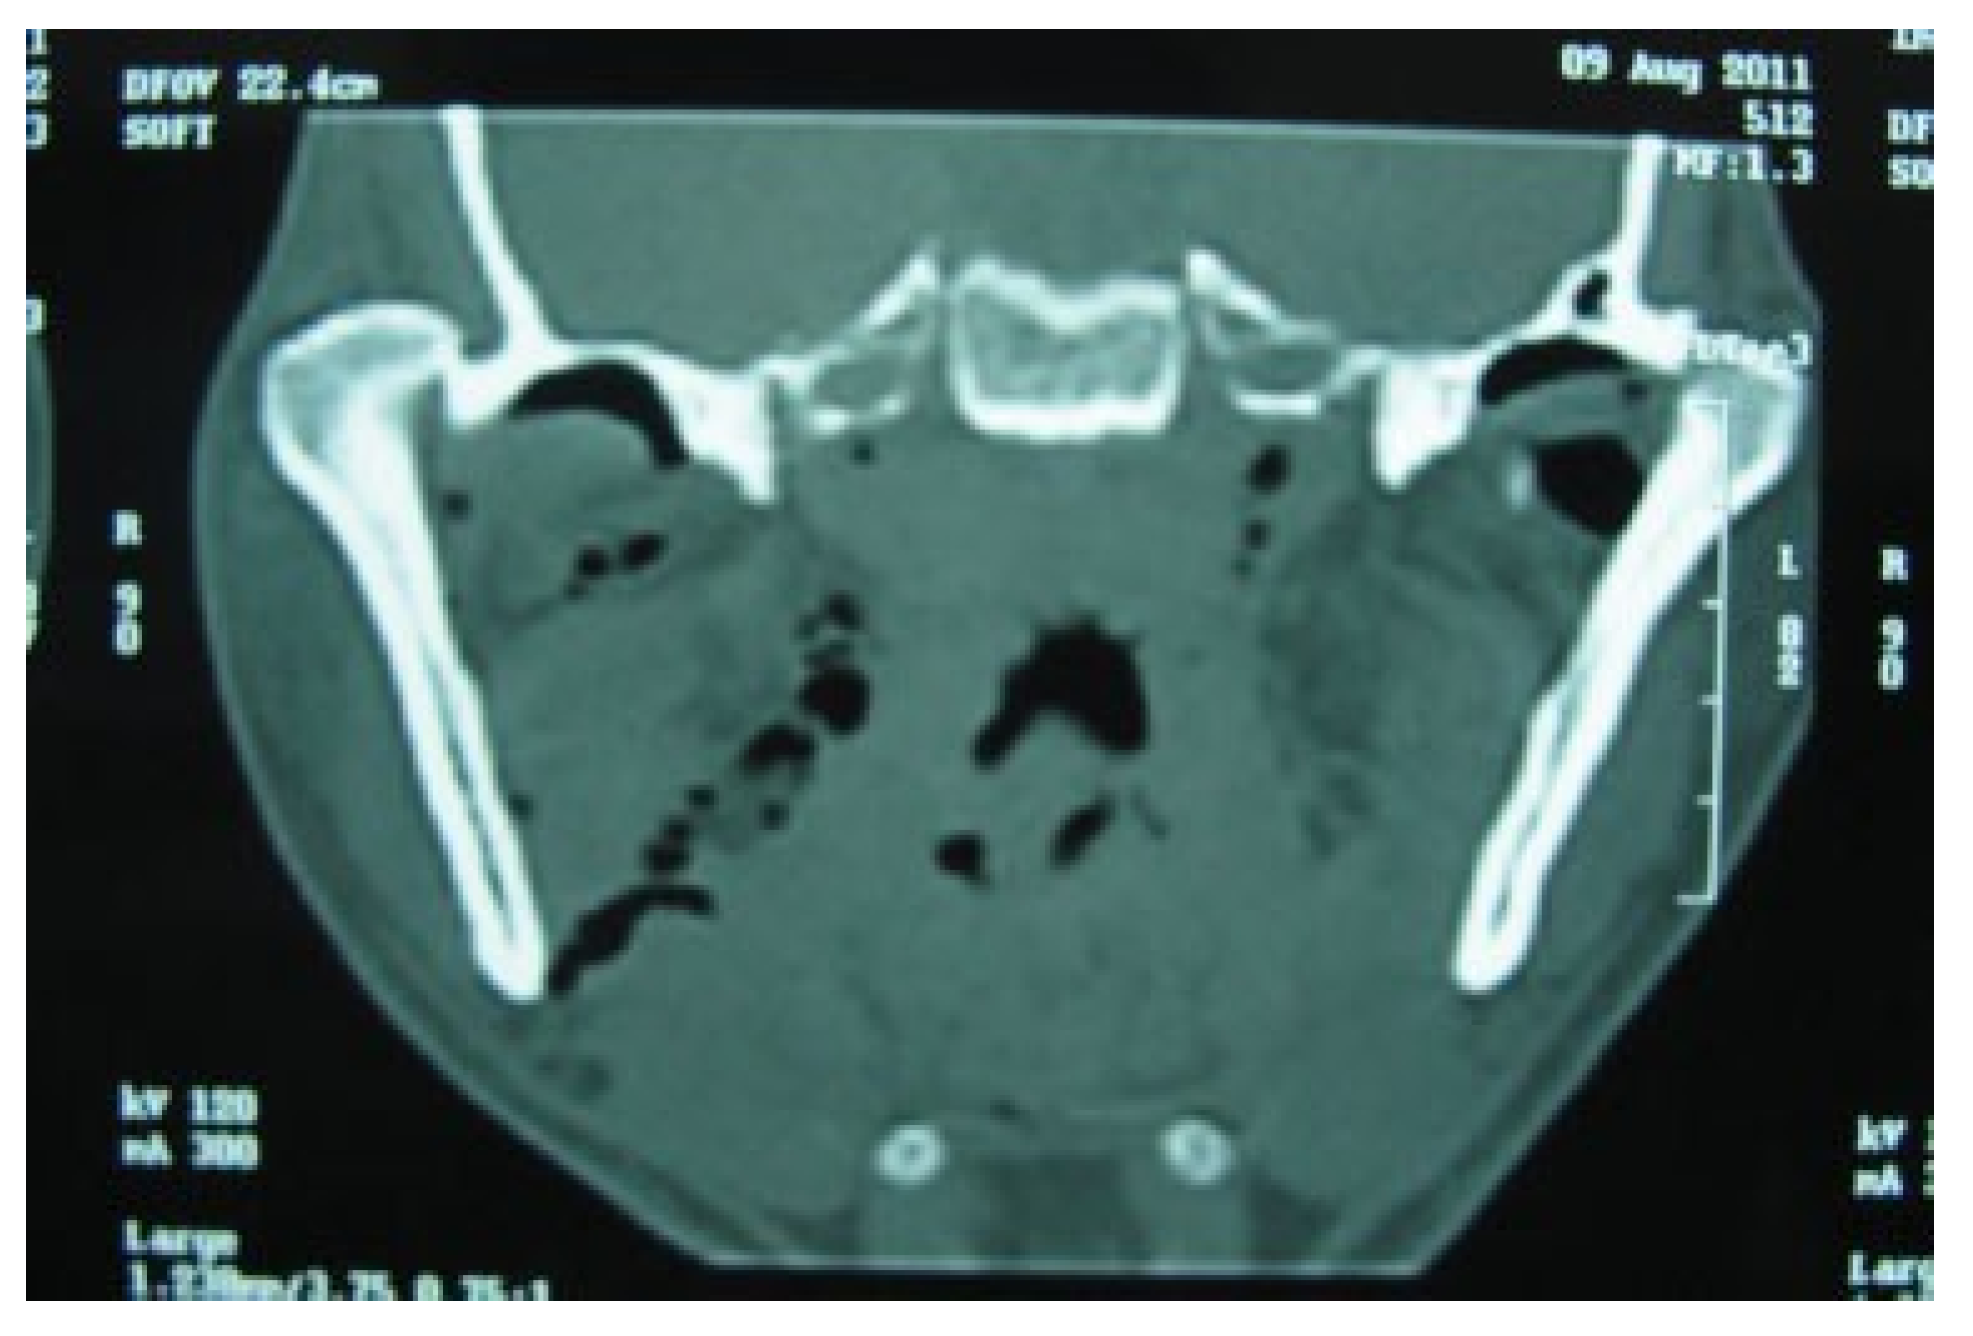

:1. Case Report